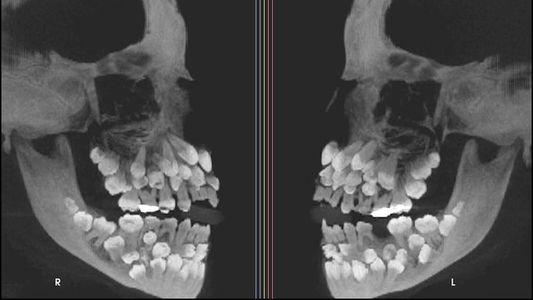

El diagnóstico fue claro desde un principio: una niña que fue al odontólogo por la cantidad de dientes. La "hiperodoncia múltiple" era evidente. Pero lo que mostró la radiografía fue cercano al horror.

En las imágenes detectaron 81 dientes: 18 caducos, 32 permanentes y 31 supernumerarios. "Los dientes supernumerarios son una anomalía del desarrollo poco frecuente que puede aparecer en cualquier zona de la arcada dental y puede afectar a cualquier órgano dental", según el sitio Informa Cosmos.

"El tratamiento ortodóncico de esta paciente fue un reto clínico por el gran número de dientes a extraer y las alteraciones en las formas de los dientes", explicaron los especialistas.